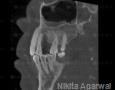

CBCT :

Yes

Pictures

Baseline